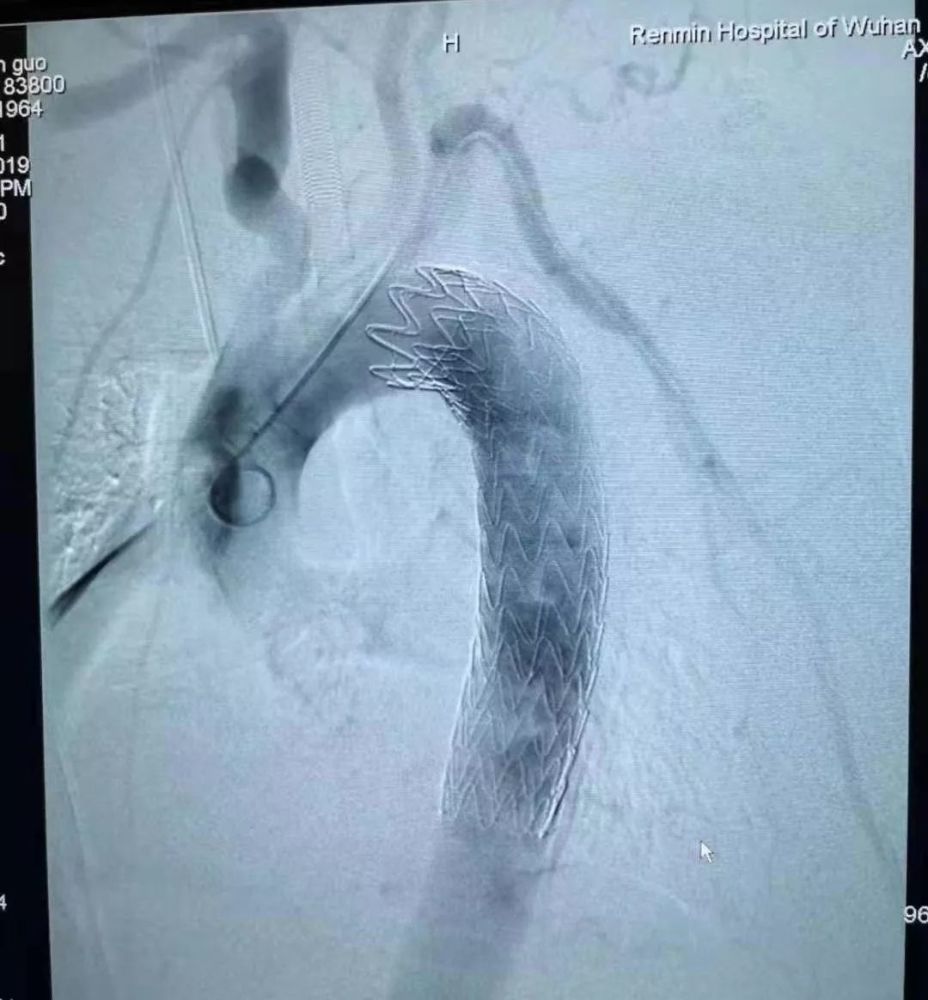

经过详细讨论 , 专家团确定了微创取刺手术方案:先由心血管外科专家为林先生植入主动脉支架堵住血管缺口 , 再由消化内科专家尝试进行消化内镜下微创取刺 。

11月29日下午 , 在麻醉医师保驾护航下 , 心血管外科吴智勇副教授首先上台 , 顺利将主动脉支架植入林先生体内 , 将已经开始糜烂的血管缺口堵牢 。 随后 , 消化内科黄旭医生开始尝试进行消化内镜下取刺 。

文章插图

图源:武汉大学人民医院